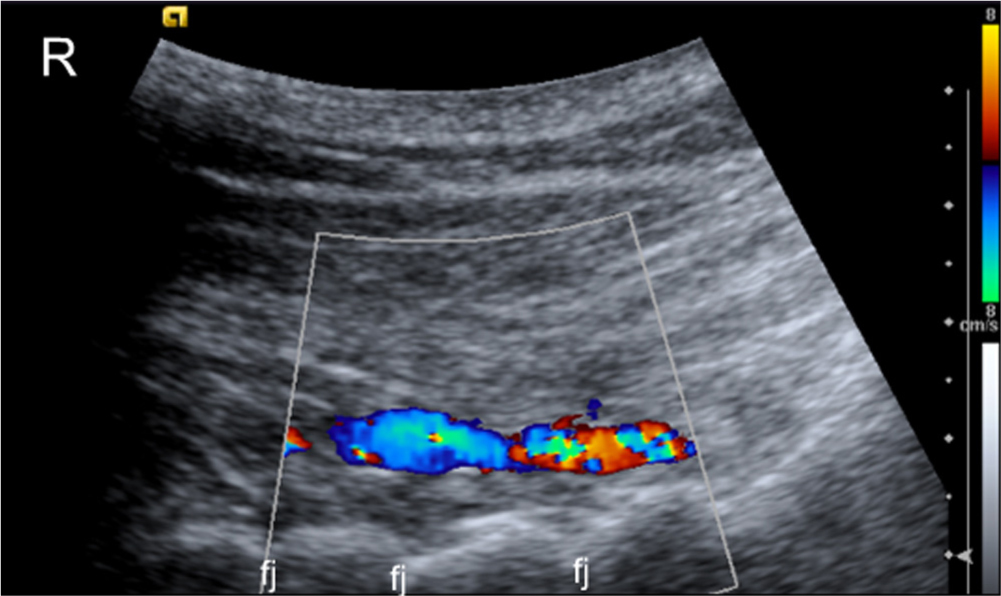

Longitudinal colour, Doppler scan of a patient with blood vessels in muscles juxtapositioned to the midcervical facet joints. Fj, facet joints; R, rostral.

Caudally to C2, the changes were similar to those observed C2 level, such that high blood flow was detected at the apices of the spinous process and bilaterally juxtapositioned to the facet joints (Figs. 4, Fig. 5, 6). In the upper cervical region from the base of the skull down to C3, high blood flow was observed more frequently in female than in male patients, totally 48 areas of change in females compared to 33 areas in males (Figs. 7 and 8, Table 1).